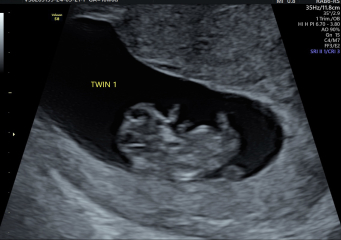

Hi everyone! We had a scan today (delayed our original early scan after we ended up at the EPU a few weeks back) and both twins are doing well and measuring at 10 weeks! It definitely feels more real now they resemble something, and we had a few little arm waves ❤️ very cute seeing them next to each other! Very ready for this nausea and exhaustion to ease up! Hope everyone else who has scans this week goes well.

OCTOBER 2024 BABIES :) THREAD 3

@journeytomum amazing news 😍 can't wait to see our twins again xxx

@journeytomum wow look at those lovely twins! Xxxx